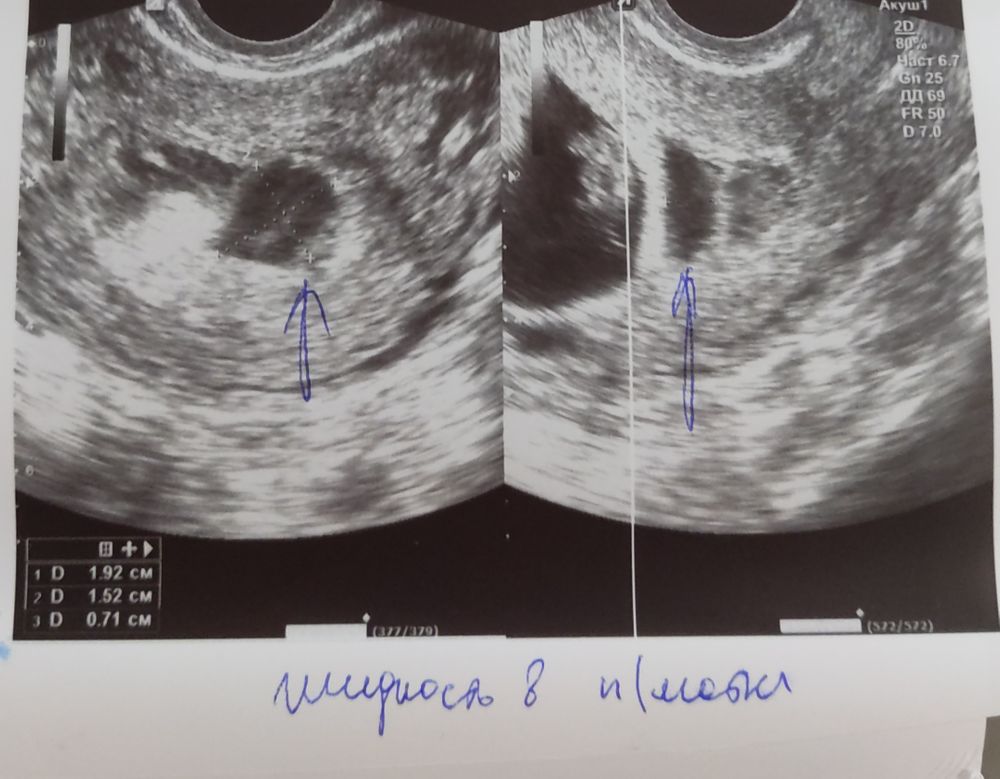

Екатерина, как у вас она выглядела на УЗИ? Вот так? Но мне не пишут гематома, жидкость

в выписке указали гематома в нижних отделах 4х3 мм